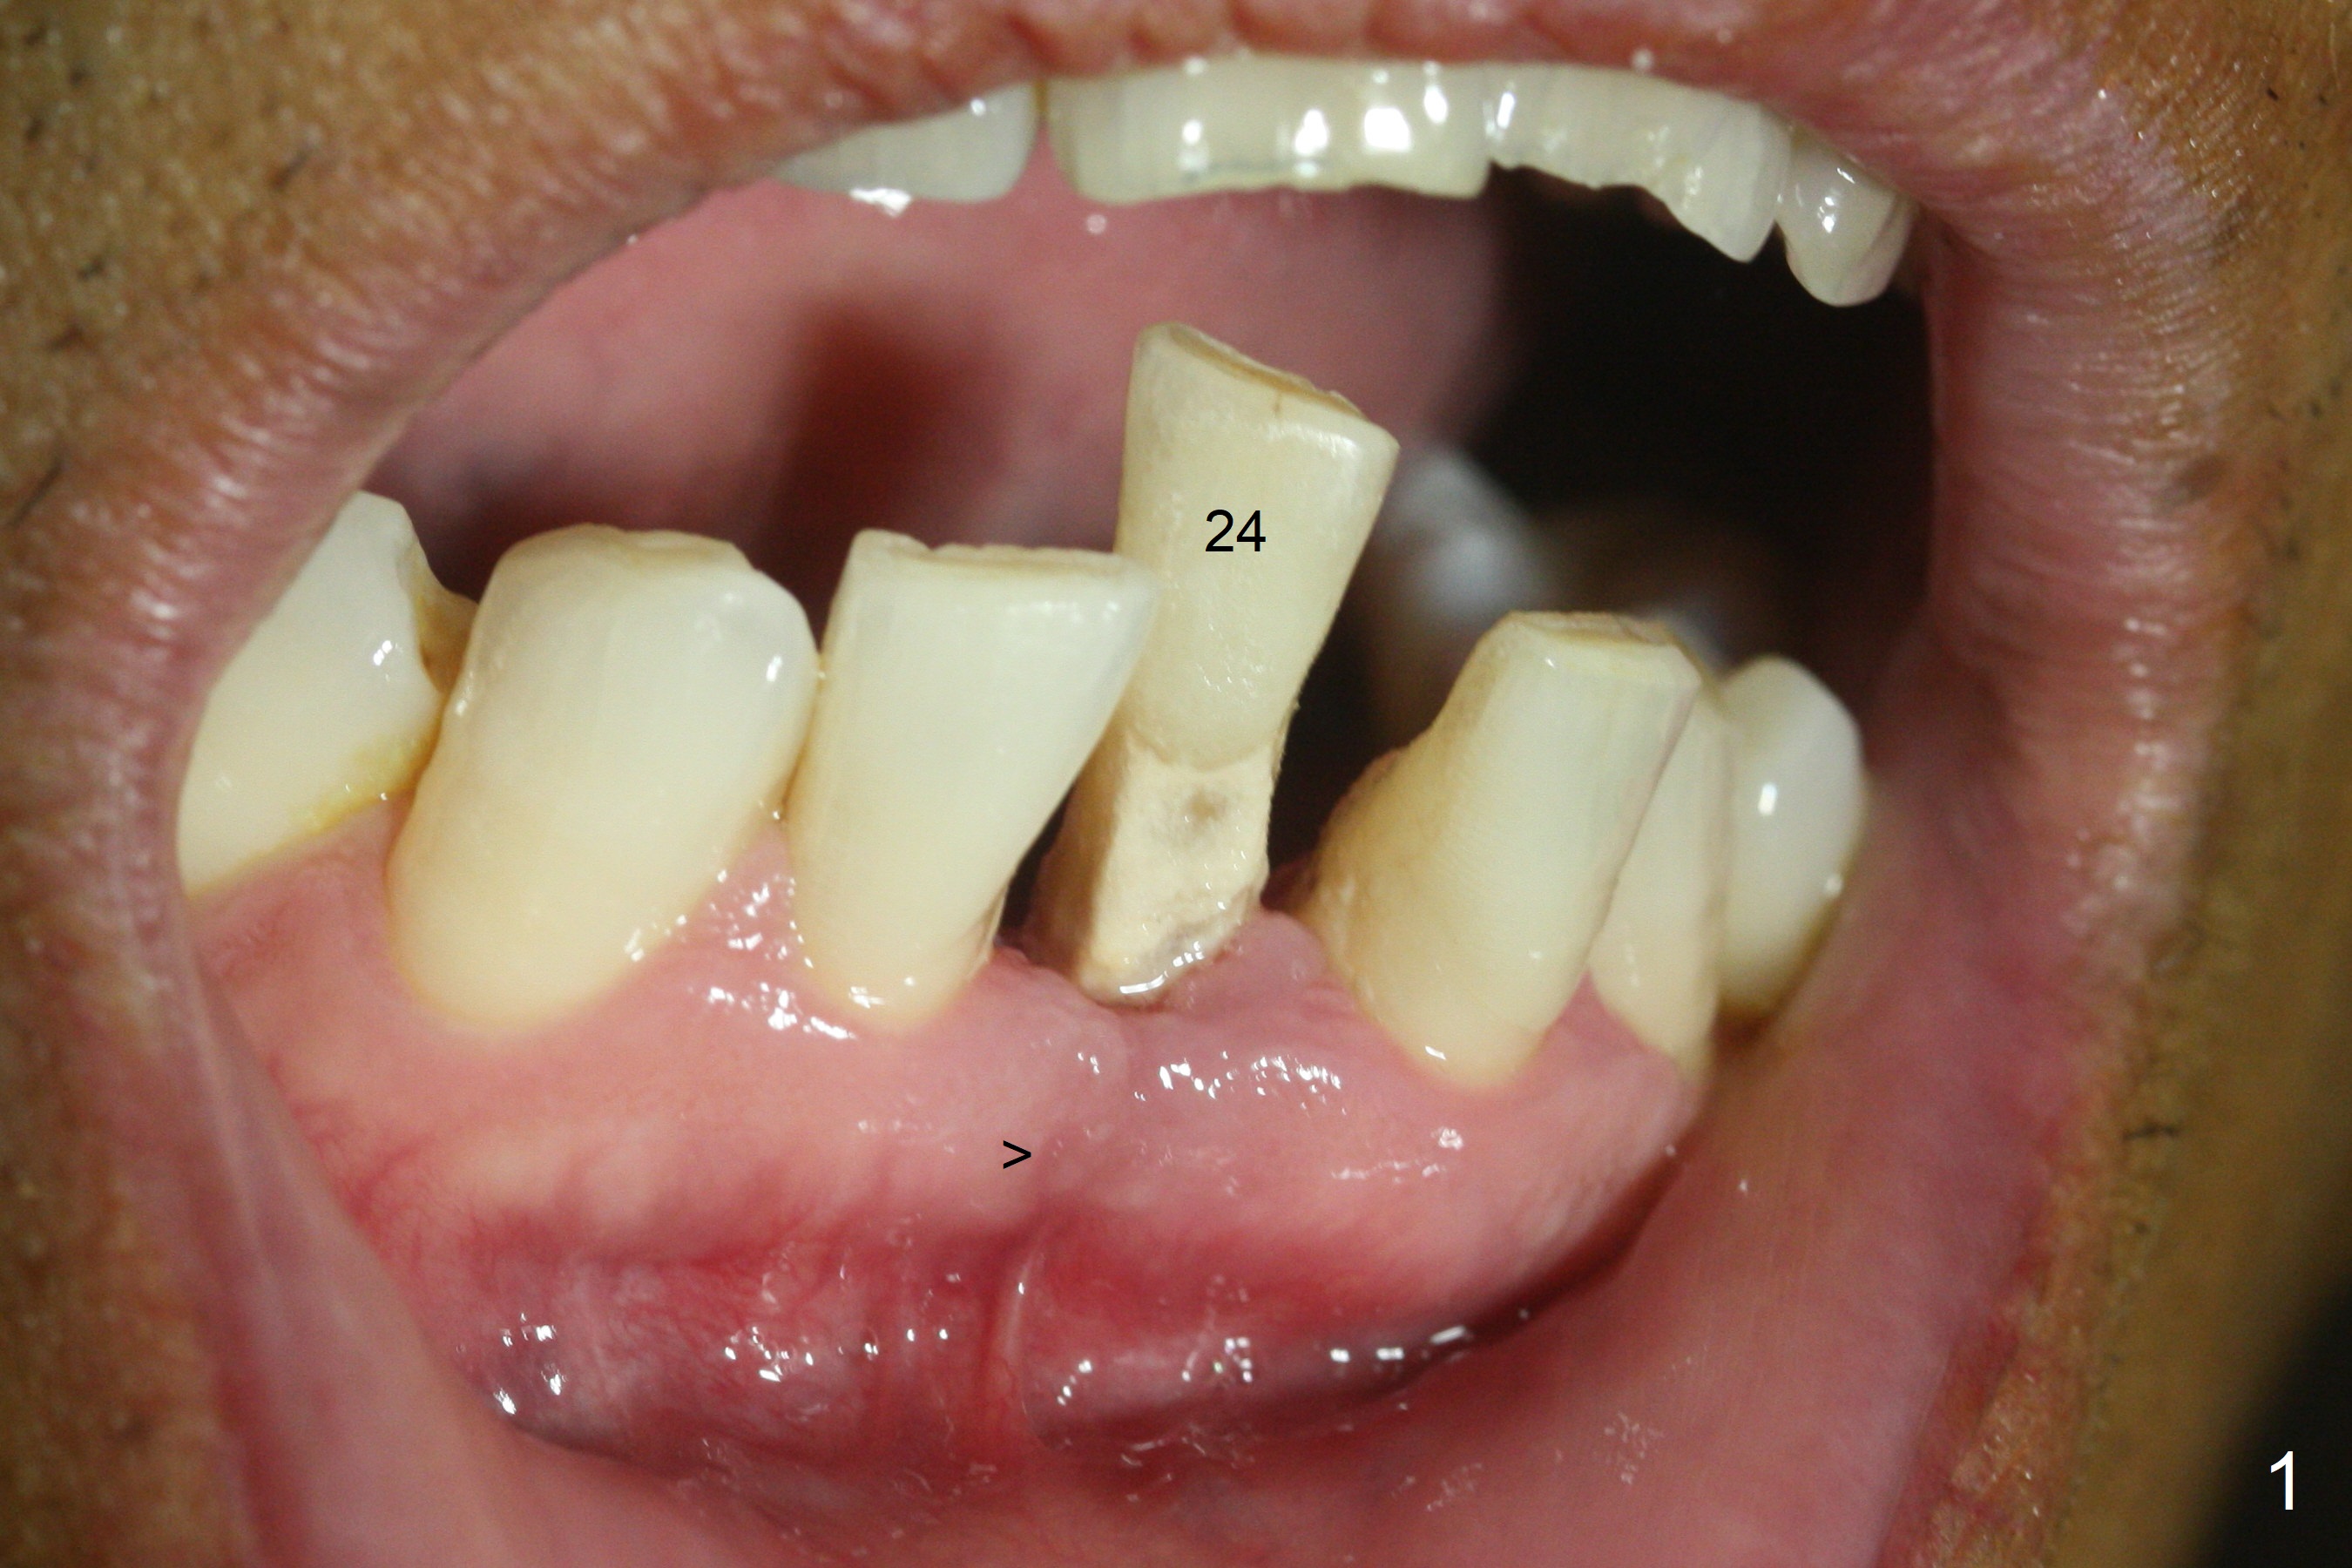

When the patient returns for implant placement 1.5 years after the last treatment (SRP), the tooth #25 has exfoliated, whereas the tooth #24 is severely displaced (Fig.1-3).  In fact the buccolingual plates are found to be lost after extraction, corresponding to change in gingival color indicated by an arrowhead in Fig.1.  Initial osteotomy with 1.2 mm drill is parallel to the terminal branches of the Incisive Canal (Fig.4 arrowheads).  Since the gingiva is as thick as 7.5 mm (Fig.3 arrow), a 3x14 mm 1-piece implant with 4 mm cuff is placed (Fig.5); three implant threads are outside the native bone; with allograft (*) placed and the neighboring crests being coronal to the threads, the chance of periimplantitis should be remote.  An immediate provisional is fabricated to contain the graft in place.  Meanwhile the tooth #2 is symptomatic with crack.  The top 3 threads appear to be contacted by the newly formed crestal bone 6 months postop (Fig.6 *).  Bone appears to have grown into the space between implant threads 6 months post cementation (13 months postop).